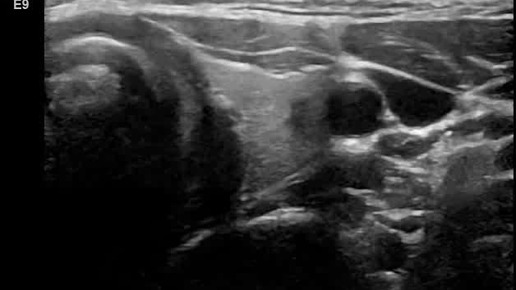

Видео к статье "Стратификация узлов щитовидной железы. TI-RADS-5" https://dzen.ru/a/ZwTJQTbM3zpM5Y6F

Ультразвуковые находки от врача УЗД Зорина Я.П.